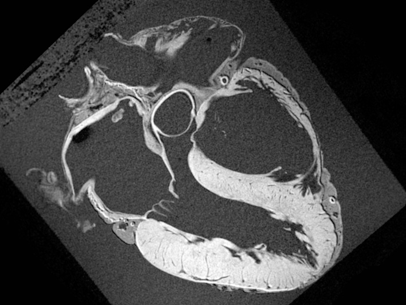

Cardiac MRI

A low-dose MRI or CT scan to look for lung cancer, pulmonary nodules, emphysema, and more. A Nanox assessment of your CT images to look for heart disease by assessing for artery plaque buildup with a coronary artery calcium (CAC) score.